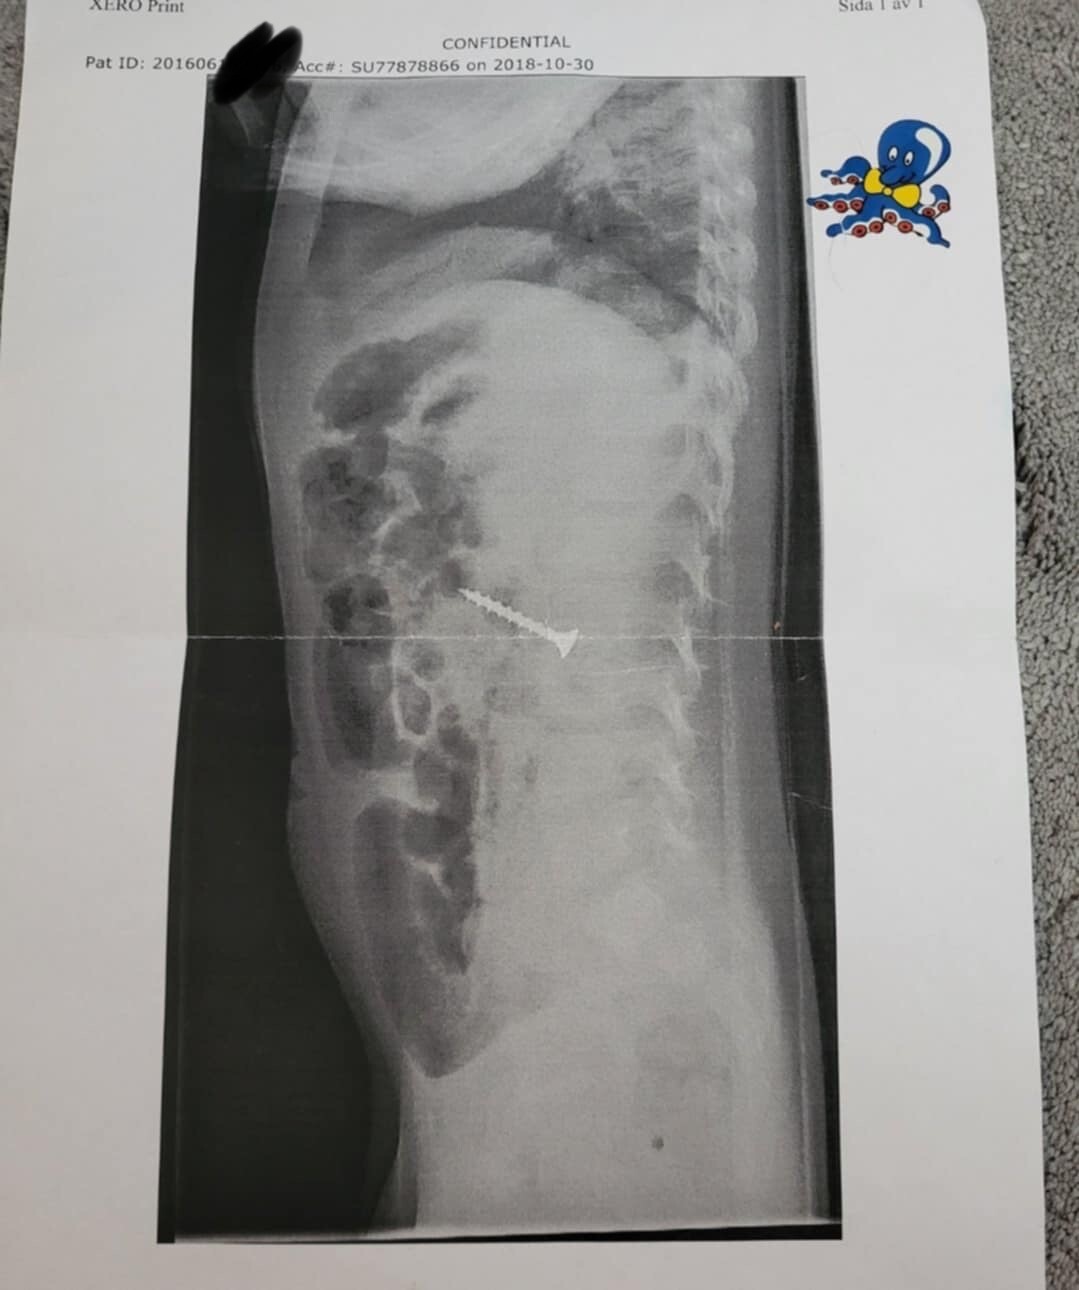

Vi renoverade med småbarn (2år). Detta blev resultatet 😬

Detta kunde givetvis undvikts, men allt kan hända och det snabbt. Det gick dock bra och nu sju år senare skrattar vi mest åt det. Men inte när det begav sig…